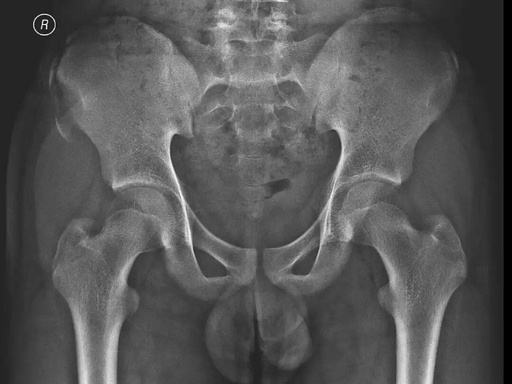

家长赶紧带他来到浙中医大二院(省新华医院)骨伤科,接诊的崔龙慷医生安排他拍了骨盆X光片。结果让大家都吃了一惊:右侧髂前上棘撕脱性骨折,一块小骨头被肌肉从骨盆上硬生生"拽"了下来。

3D图片示意

髂前上棘撕脱骨折X片